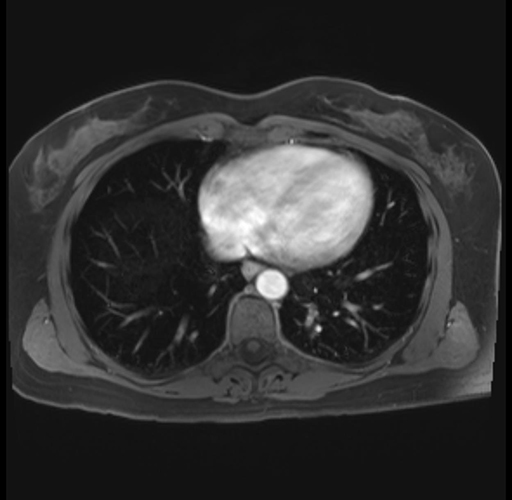

Imaging Analysis

Look through the patient's CT scan to identify any areas of concern for the necessary procedure.

Based on your CT findings, which issue(s) are present and would give reason for "planned slowing down moment(s)" in this case?